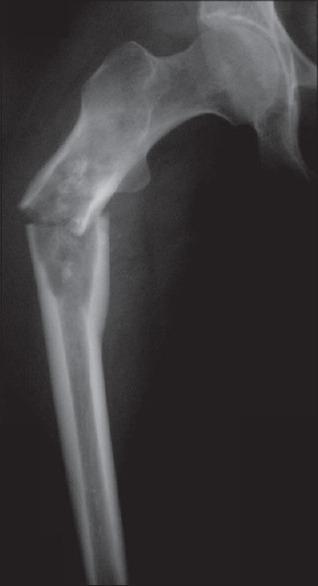

Skeletal metastasis is a common cause of severe morbidity, reduction in quality of life (QOL) and often early mortality. Its prevalence is rising due to a higher rate of diagnosis, better systemic treatment, longer lives with the disease and higher disease burden rate. As people with cancer live longer and with rising sensitivity of body imaging and surveillance, the incidence of pathological fracture, metastatic epidural cord compression is rising and constitutes a challenge for the orthopedic surgeon to maintain their QOL. Metastatic disease is no longer a death sentence condemning patients to "terminal care." In the era of multidisciplinary care and effective systemic targeted and nontargeted therapy, patient expectations of QOL, even during palliative end of care period is high. We lay emphasis on proving the diagnosis of metastasis by biopsy and histopathology and discuss imaging modalities to help estimate fracture risk and map disease extent. This article discusses at length the evidence and decision-making process of various modalities to treat skeletal metastasis. The modalities range from radiation including image-guided, stereotactic and whole body radiation, systemic targeted or hormonal therapy, spinal decompression with or without stabilization, extended curettage with stabilization, resection in select cases with megaprosthetic or biological reconstruction, percutaneous procedures using radio frequency ablation, cementoplasties and discusses the role of emerging modalities like high frequency ultrasound-guided ablation, cryotherapy and whole body radionuclide therapy. The focus lies on the role of multidisciplinary care, which considers complex decisions on patient centric prognosis, comorbidities, cost, feasibility and expectations in order to maximize outcomes on QOL issues.

骨转移是导致严重发病、生活质量(QOL)下降以及常出现早期死亡的常见原因。由于诊断率提高、全身治疗效果更好、患者带病生存时间延长以及疾病负担率上升,其患病率正在上升。随着癌症患者生存期延长以及身体成像和监测的敏感性提高,病理性骨折、转移性硬膜外脊髓压迫的发生率正在上升,这对骨科医生维持患者的生活质量构成了挑战。转移性疾病不再是宣判患者“临终关怀”的死刑判决。在多学科护理以及有效的全身靶向和非靶向治疗时代,即使在姑息性临终关怀阶段,患者对生活质量的期望也很高。我们强调通过活检和组织病理学来证实转移瘤的诊断,并讨论有助于评估骨折风险和描绘疾病范围的成像方式。本文详细讨论了治疗骨转移的各种方式的证据和决策过程。这些方式包括放疗,如影像引导放疗、立体定向放疗和全身放疗、全身靶向或激素治疗、有或无内固定的脊柱减压、扩大刮除术加内固定、在某些病例中进行假体或生物重建的切除术、使用射频消融、骨水泥成形术的经皮手术,并讨论了高频超声引导消融、冷冻疗法和全身放射性核素治疗等新兴方式的作用。重点在于多学科护理的作用,它考虑以患者为中心的预后、合并症、成本、可行性和期望等复杂决策,以最大限度地提高生活质量相关问题的治疗效果。